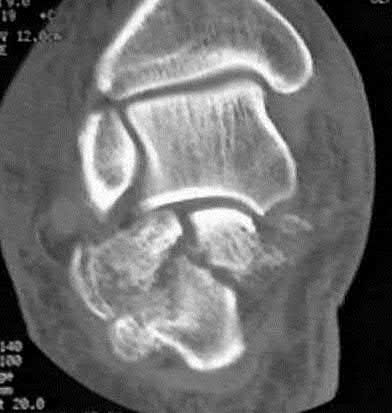

A 35 year-old female presents after prolonged extrication from a motor vehicle collision complaining of severe pelvic pain. Physical examination reveals diminished perianal sensation. She is otherwise neurologically intact. Figures A through D are radiographs and representative CT cuts of her injury. Which of the following nerve roots has likely been injured by the acute trauma?

The clinical scenario is consistent with a high-energy sacral fracture. The radiographs in figures A and B demonstrate a sacral fracture with posterior displacement of the right hemipelvis seen on the inlet view. Figures C and D are axial and sagittal CT images which show a displaced fracture of the right

hemisacrum along with a transvere fracture component through the S3 body . Diminished perianal sensation is concerning for an S2 nerve root injury.

Mehta et al reviewed the current management of sacral fractures. They note that the S1 and S2 nerve roots are more likely to be injured with sacral fractures as they occupy 1/3 to 1/4 of the neural foramina, as opposed to S3 and S4, which only occupy 1/6 of the neural foramina.

Robles reviewed the current literature to ascertain principles of evaluation and treatment for transverse sacral fractures. The author notes that injury to nerve roots S2 to S5 is manifested by impairment of urinary and anal continence and sexual function.

The first illustration demonstrates the sacral nerve root dermatomal distribution. The second shows a pelvic cadaver dissection demonstrating the sacral nerve roots as they exit the foramina.